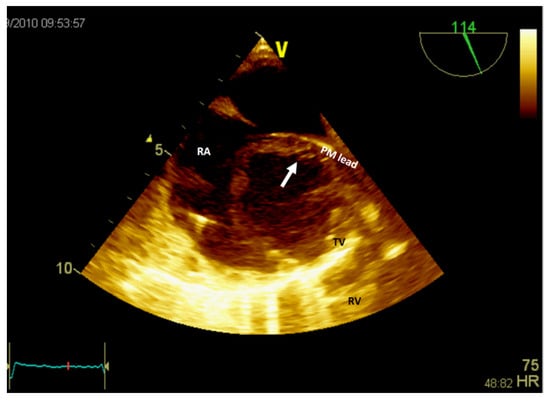

Figure 6.

Two-dimensional transesophageal echocardiography (short-axis view at the level of the great vessels) showing a mass (arrow) in the right atrium on the pacemaker leads. PM, pacemaker; RA, right atrium; RV, right ventricle; TV, tricuspid valve.

If the patient has a pacemaker or automatic implantable defibrillator, the first supposition in a clinical context suggestive of endocarditis is vegetation (Figure 6, Video S3—Supplementary Materials). A differential diagnosis must include fibrin formations or thrombi. However, if the patient is already anticoagulated (due to atrial fibrillation), these diagnoses are less likely.